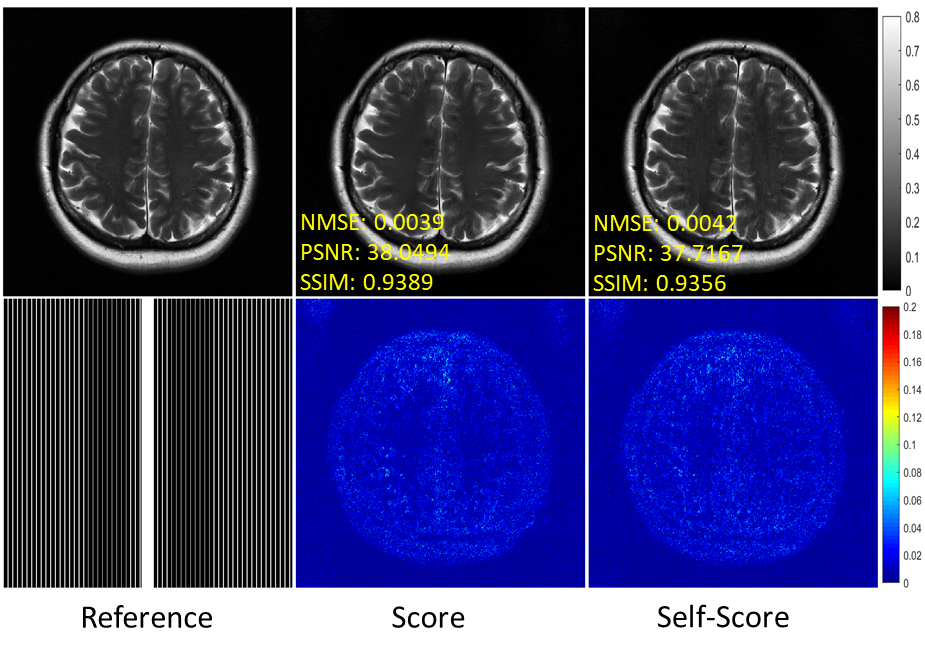

6.1 Comparison Experiment with Conventional Score-Based Method

Theoretically, the accuracy of the proposed method regarding the estimation of data distribution depends mainly on Assumption 1. Although it is a natural generalization of ”linear predictability” and ”translational invariance” in k𝑘k-space interpolation methods, there may still be some cases where it is not fully accurate. Therefore, we designed comparison experiments with the conventional score-based diffusion method trained on fully sampled data to verify the accuracy of the proposed self-supervised learning method on the data distribution estimation.

Figure 7 shows the reconstruction results of the conventional score-based method (termed score) and our proposed self-supervised score-based method (termed self-score) for fastMRI knee and SIAT brain data under 6-fold and 4-fold uniform undersampling, respectively. In terms of visual perception, the two methods perform almost identically. The quantitative metrics are shown in Table 4. It can be found that the proposed self-score method performs almost identically to the score method on the fastMRI knee dataset and even slightly better than the score on the SIAT brain dataset. This experiment validates the accuracy of the proposed self-supervised learning method for data distribution estimation.

Refer to caption

Figure 7: Reconstruction of the fastMRI knee (first two rows) and SIAT brain (last two rows) data at uniform undersampling of R=6𝑅6R=6 and R=4𝑅4R=4, respectively. The values in the corner are NMSE/PSNR/SSIM values. Second and fourth rows illustrate the enlarged views. The grayscale of the reconstructed images is at the right of the figure.

We also compared the generalization capabilities of the two methods described above, i.e., trained on the fastMRI knee dataset but applied to reconstruct 6-fold uniformly undersampled fastMRI brain MR images. From the results presented in Figure 8, we can find that the proposed self-supervised score-based method trained on undersampled data performs very close to the method trained on fully sampled data in terms of the visual perception and error of the reconstructed images. The above experimental result further validates the accuracy of the proposed self-supervised learning method for estimating the distribution of the fully sampled MRI data.

Figure 8: Reconstruction of the fastMRI brain at uniform undersampling of R=6𝑅6R=6. The values in the corner are NMSE/PSNR/SSIM values. Second row illustrates the error view. The grayscale of the reconstructed images and the color bar of the error images are at the right of the figure.